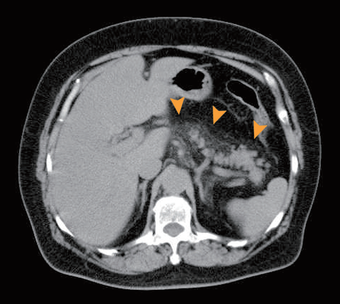

【急性膵炎】

膵臓の炎症がその周囲組織に波及している。